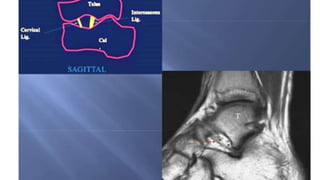

Syndesmotic ligament:

• Between distal tibia and fibula.

• Anterior syndesmosis: Anterior-inferior-tibio-fibular ligament (AITiFL)

is basically connecting Chaput tubercle of tibia to Wagstoffes tubercle

of fibula.

• Middle syndesmosis: Interosseous tibiofibular ligament.

• Posterior syndesmosis: Triangular shaped poster-inferior-tibio-fibular

ligament (PITiFL).